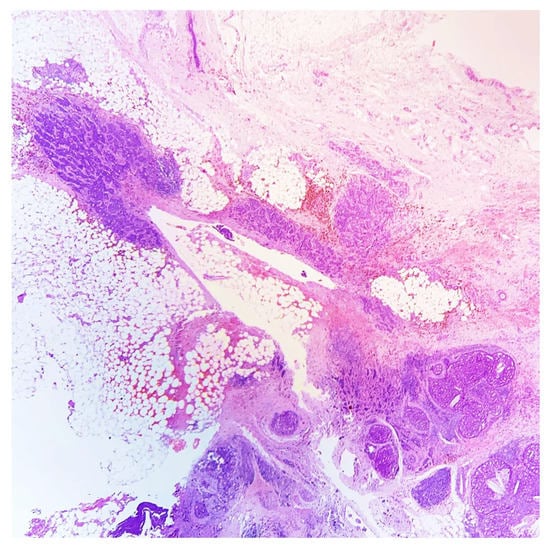

A 45-year-old lady, during her screening ultrasonography, was found to have an 8-millimeter solid mass in the upper outer quadrant of right breast, characterized by irregular margins and inhomogeneous internal echoes, suspicious for carcinoma. An ultrasound-guided core needle biopsy of the lesion was performed and a diagnosis of gland-forming breast carcinoma with many erythrocytes, hemosiderin, and stromal osteoclast-like giant cells was rendered. The neoplastic cells showed a moderate grade of atypia. No further assays were performed (Figure 1 and Figure 2).

Figure 1. Ultrasound-guided core needle biopsy showing invasive breast carcinoma, associated with hemosiderin deposition (HE, 100×).